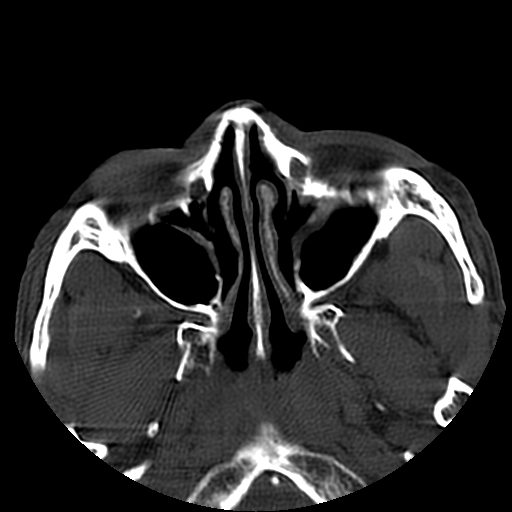

以下是引用liaoqiang在2008-7-16 21:15:00的发言:[br]右侧鼻骨骨折

以下是引用zxd95在2008-7-16 21:39:00的发言:[br]右侧上颌骨额突骨折。[br][br][br][br]